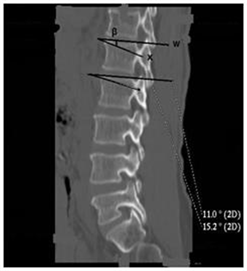

Figure 4. Sagittal section of the lumbar spine passing through the pedicles (beta angle). w: tangent to the upper plate of the vertebral body; x: axis of inclination of the vertebral pedicle on the horizontal; β: angle of inclination of the pedicle axis with respect to the horizontal plane.

The length of the pedicle decreased from L1 to L5 and there was no significant difference between the left and the right or between the man and the woman (p = 0.1). Pedicle width increased from L1 to L5 and was the same between left and right. Values in men were significantly higher than in women (p ˂ 0.001). The alpha angle increased from L1 to L5 (Figure 3). There was no significant difference between the left and right or between the man and the woman (p = 0.07). The beta angle (Figure 4) decreased from L1 to L5. The difference between the man and the woman was not statistically significant (p = 0.3).

Thus in our series, the length of the pedicle decreased from L1 to L5 and there was no significant difference by sex or vertebral side. The width, unlike the length, increased significantly from L1 to L5. There was no significant difference between left and right. However, it was greater in men than in women. The alpha angle of inclination of the pedicle axis with respect to the sagittal plane became more and more obtuse from L1 to L5. There was no significant difference between left and right or between the man and the woman. As for the angle beta of the axis of the pedicle with respect to the upper plate of the vertebral body, it became more and more acute from L1 to L5 and varied on average from 14.2 degree in L1 to 8.8 degree in L5. The difference between the man and the woman was not statistically significant although the values in humans seem smaller.